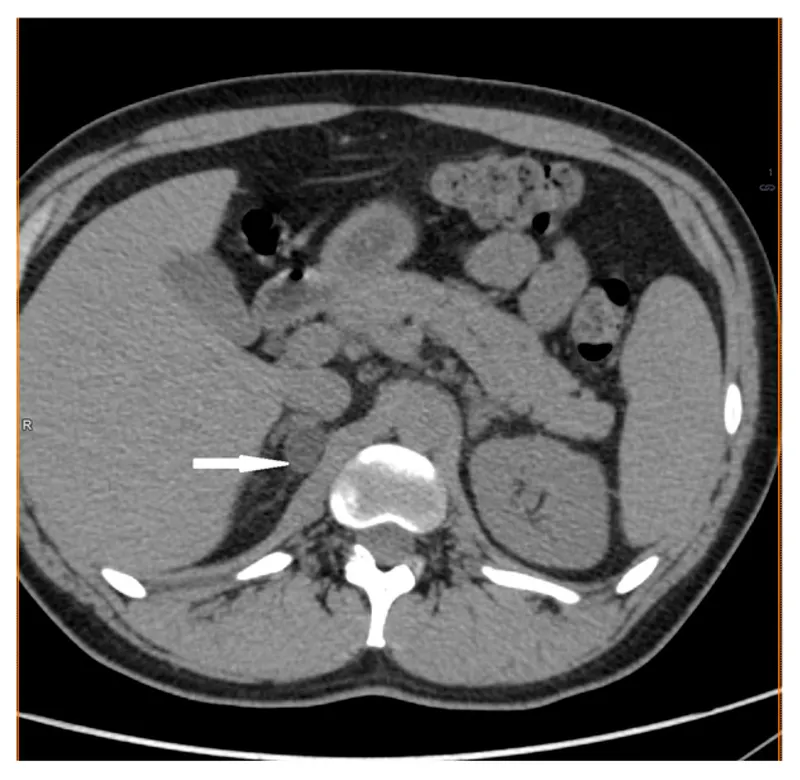

Pheochromocytoma: Catecholamine-secreting tumor of the adrenal medulla.

- Dx: ↑ 24-hr urine & plasma metanephrines.